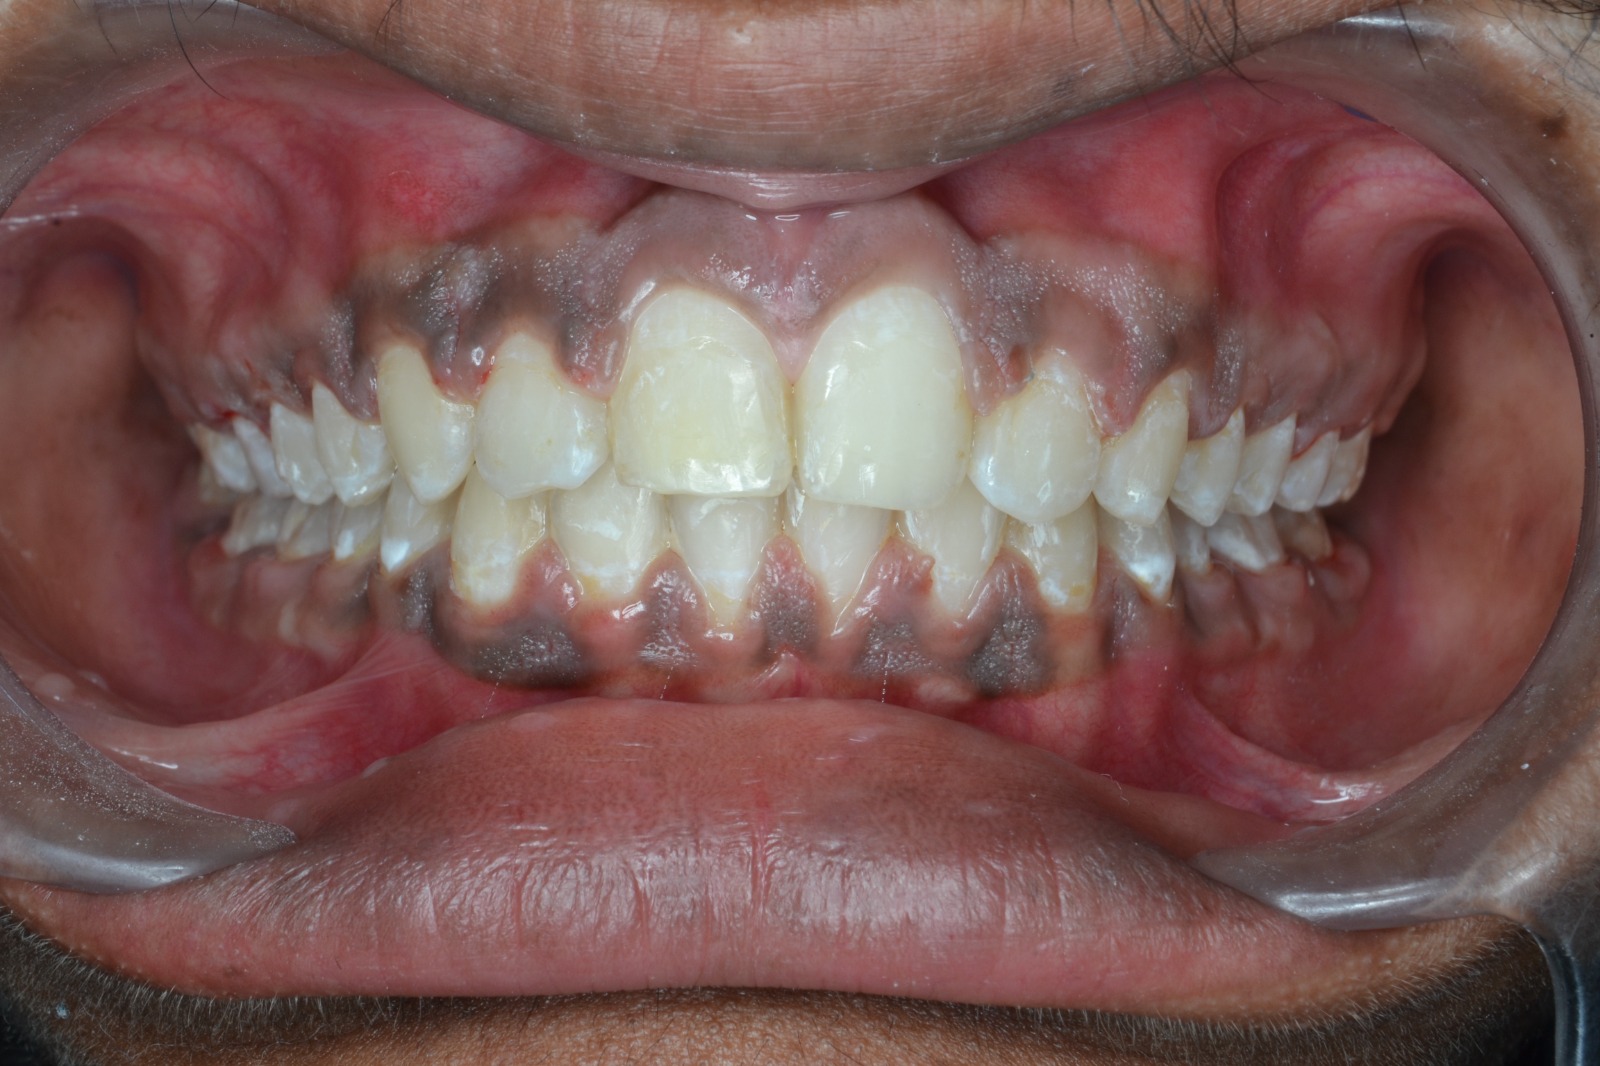

After/Before

See stunning smile transformation before and after

Before After